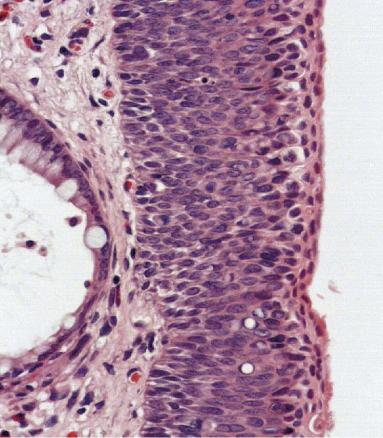

L’examen clinique révèle un placard érythémateux, bilatéral en « ailes de papillon », à contours irréguliers, discrètement squameux, avec des condylomes (fig. 1).

Les symptômes d’appel sont non spécifiques : prurit, saignement, suintement… De surcroît, l’aspect est polymorphe et volontiers trompeur, avec des papules cutanées érythémateuses, des pseudopapillomes plus ou moins exophytiques et/ou des plaques kératosiques bistre ou rosées, uni- ou multifocales, susceptibles de s’étendre.